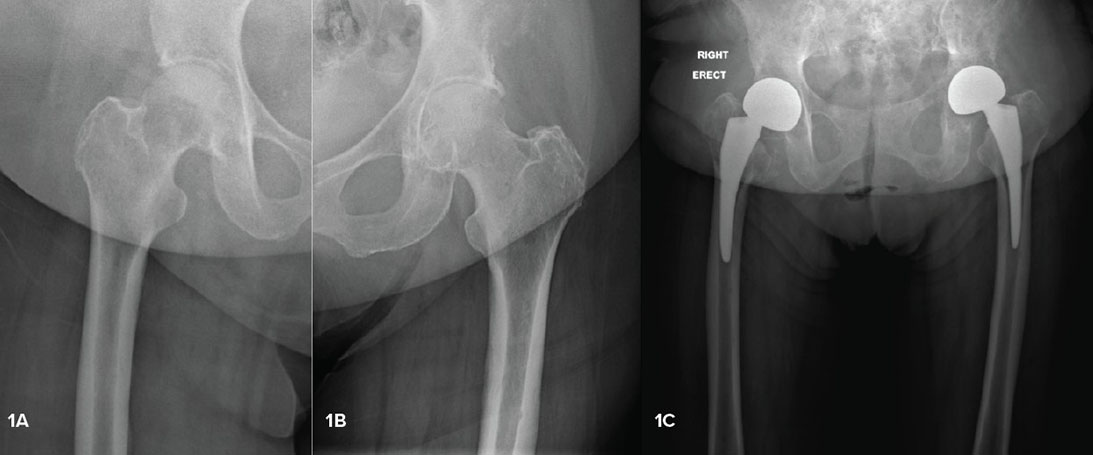

Hip replacement in metastatic disease: Guidance for the non-oncology surgeon

Orthopaedic surgeons will increasingly be needed to care for oncology patients with pathologic fractures, infection, and other complications.